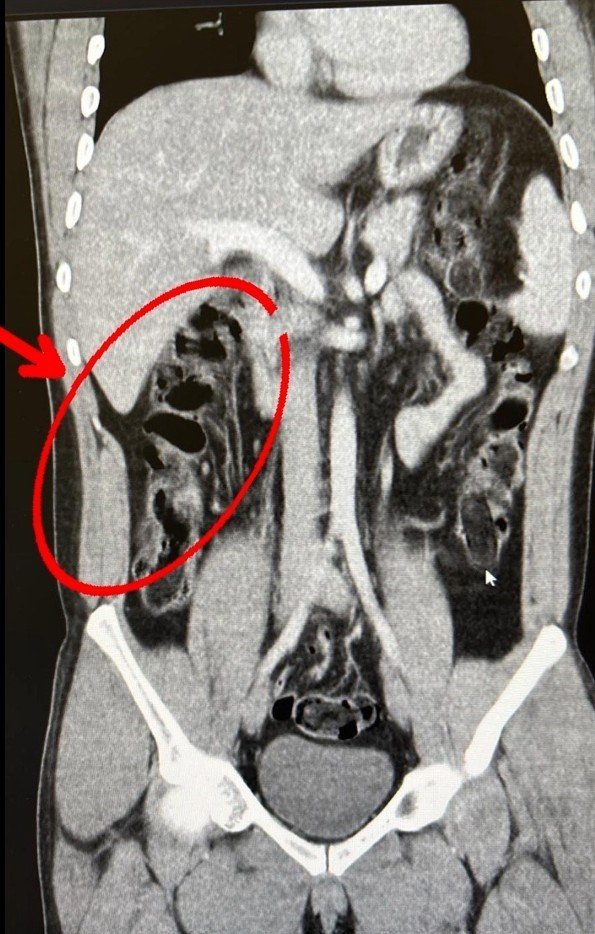

S.S. ve F.M.K. isimli şahısların hastanede yapılan iç beden muayenesi sonucunda 35 kapsül halinde toplam 278 gram eroin maddesi ele geçirildi. Şüphelilerin havalimanındaki görüntüleri, yakalandıktan sonra muayene edilme anları ve yuttukları kapsüllerin yer aldığı film sonuçları kameralara yansıdı. 2 şüpheli, "uyuşturucu veya uyarıcı madde ticareti yapmak ve sağlamak" suçundan adli makamlarca tutuklandı.